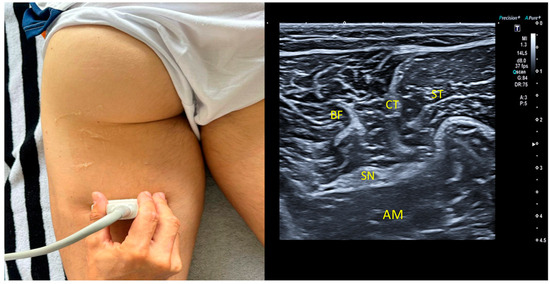

2.5. Ultrasound Imaging Procedure: Sciatic Nerve

2.7. Mid-Third Measurement